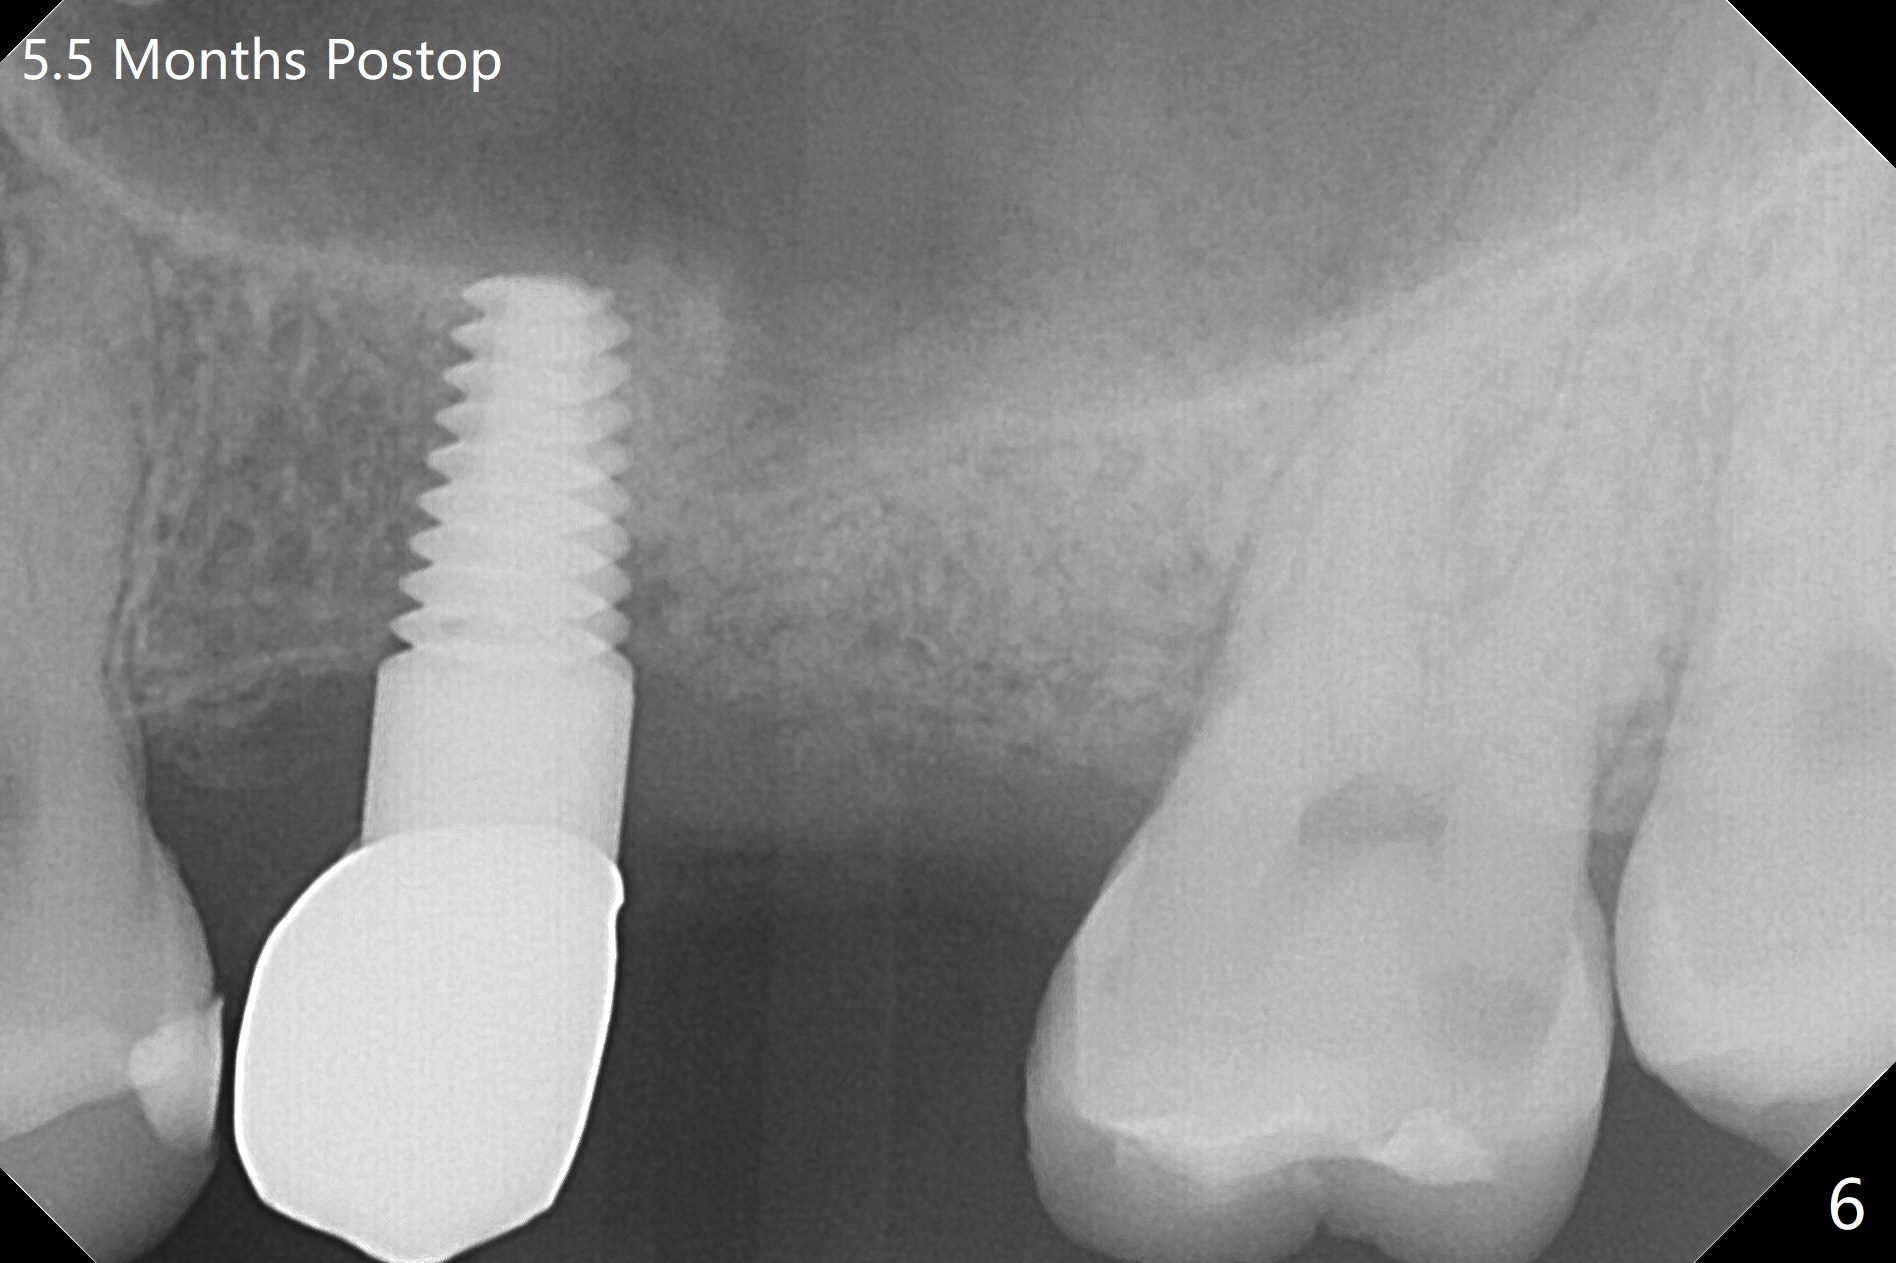

A 32-year-old woman develops periimplantitis (severe hemorrhage and deep pockets) at #14 three years 7 months post cementation (Fig.1).  A 4.5x11 mm implant is placed with flap at #13 after failure for the 1st time (Fig.2), while a 5x11 mm implant is placed flapless with sinus membrane perforation.  Uniposts are cemented with Ketac.  The lingual plate at #14 is defective (Fig.3).  The implant at #14 will be removed flapless, followed by Osteogen plug (most likely sinus floor defect) and bone graft.  After healing, an implant will be placed with guide.  By breaking the proximal contacts, the crown, abutment and implant at #14 are shaken loose using forceps.  Finally the crown breaks off.  Make a slot on the top of the abutment and use a screw bit to turn the abutment/implant counterclockwise.  There is abundant granulation tissue with arterial hemorrhage associated with granulation tissue removal.  The defect involves the distal surface of the implant at #13 and the mesial surface of the tooth #15.  Therefore bone graft is deposited in these surfaces (Fig.4 arrowheads, as compared to preop BW, Fig.4').  The periodontal dressing seems to remain in place asymptomatic 7 days postop (Fig.5).  The bone height 5.5 months postop should be enough for implantation (Fig.6).  To avoid marker associated with guided surgery, free hand will be adopted.  Sinus lift with PRF is expected.  To place in the middle of the ridge buccopalatally, incision will be made with bone expansion.